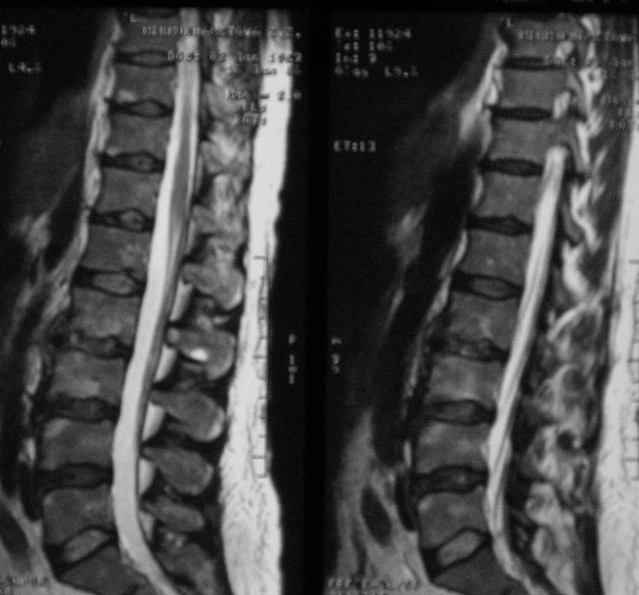

Отправляю MRI в динамике, снятые с пленки на фотоаппарат.